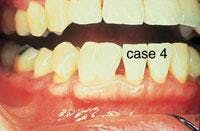

CASE 4

Fusion

1. What causes fusion?

a. tetracycline use

b. crowding

c. trauma

d. both b & c

2. Identify the true statement concerning fusion.

a. permanent dentition affected most often

b. results in an increased number of teeth

c. anterior teeth affected most often

d. premolars affected most often

3. Identify the true statement(s) concerning the appearance of fusion.

a. one large crown with observable separation

b. size may range from normal to twice normal

c. clinically resembles a geminated tooth

d. all of the above